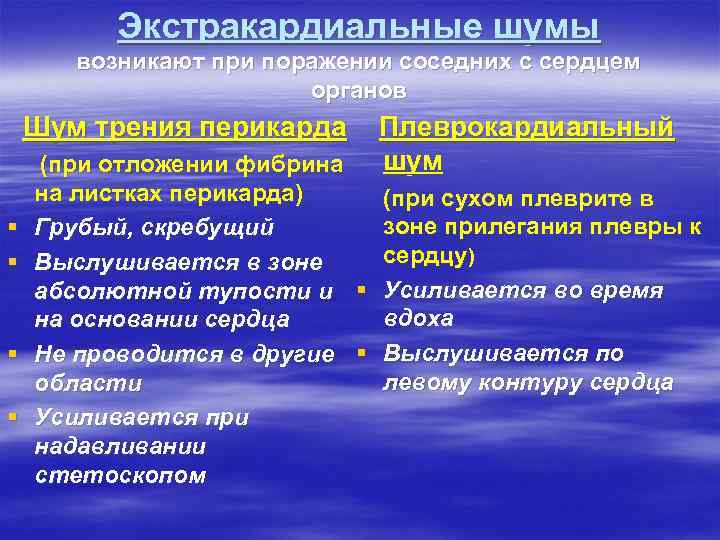

Экстракардиальные шумы возникают при поражении соседних с сердцем органов Шум трения перикарда § § Плеврокардиальный шум (при отложении фибрина на листках перикарда) (при сухом плеврите в зоне прилегания плевры к Грубый, скребущий сердцу) Выслушивается в зоне абсолютной тупости и § Усиливается во время вдоха на основании сердца Не проводится в другие § Выслушивается по левому контуру сердца области Усиливается при надавливании стетоскопом

Экстракардиальные шумы возникают при поражении соседних с сердцем органов Шум трения перикарда § § Плеврокардиальный шум (при отложении фибрина на листках перикарда) (при сухом плеврите в зоне прилегания плевры к Грубый, скребущий сердцу) Выслушивается в зоне абсолютной тупости и § Усиливается во время вдоха на основании сердца Не проводится в другие § Выслушивается по левому контуру сердца области Усиливается при надавливании стетоскопом